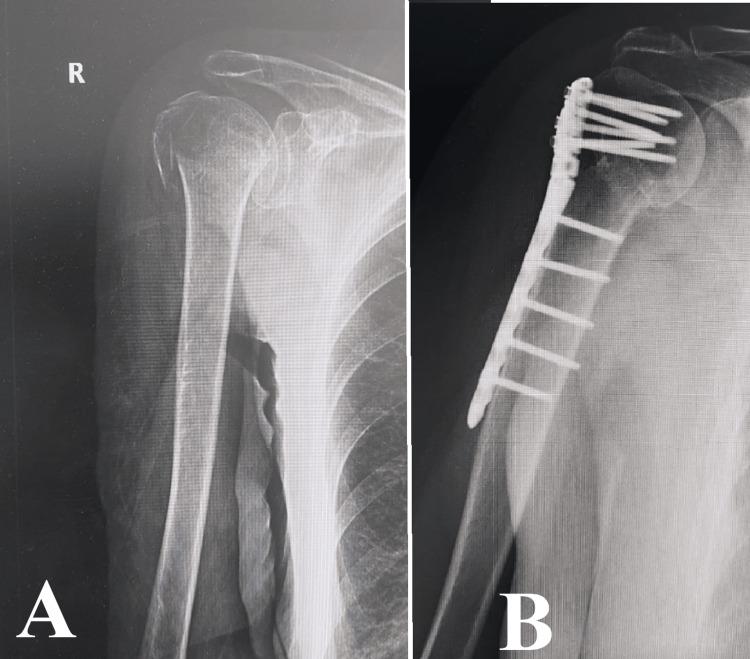

Managing osteoporotic fractures in older individuals is a difficult task in orthopedic surgery. It requires a careful approach that combines advanced diagnostic methods, customized surgical treatments, and comprehensive rehabilitation strategies. This article presents the results of an analysis carried out at the University Emergency Hospital, Bucharest. The analysis specifically examines the treatment of osteoporotic fractures using different osteosynthesis techniques. Although diagnostic tools like dual-energy X-ray absorptiometry (DXA) and Fracture Risk Assessment Tool (FRAX) have improved, a considerable number of fractures still happen in people who do not have obvious osteoporosis. This emphasizes the importance of using additional diagnostic measures such as high-resolution peripheral quantitative computed tomography (HR-pQCT) and quantitative computed tomography (QCT) to improve the accuracy of predictions. The study demonstrates the intricate nature of surgical decision-making and the significance of adjusting techniques to meet the specific needs of each patient. An instance of osteosynthesis failure resulting from the inappropriate choice of method highlighted the crucial significance of a thorough preoperative assessment. The discussion highlights the importance of early mobilization and rehabilitation in reducing the risks associated with prolonged immobilization and improving patient recovery. This paper strongly supports the use of evidence-based and patient-centered methods in the management of osteoporotic fractures. It emphasizes the importance of utilizing the most recent advancements in diagnostic and surgical technologies. Promising advancements in orthopedic medicine lie in the future, particularly in the integration of interdisciplinary research and personalized medicine. These advancements have the potential to enhance patient outcomes in this population that is at high risk.

在老年个体中处理骨质疏松性骨折是骨科手术中的一项艰巨任务。这需要一种谨慎的方法,将先进的诊断方法、定制的手术治疗和全面的康复策略结合起来。本文介绍了在布加勒斯特大学急诊医院进行的一项分析结果。该分析具体研究了使用不同骨固定技术治疗骨质疏松性骨折的情况。尽管双能X线吸收法(DXA)和骨折风险评估工具(FRAX)等诊断工具有所改进,但在没有明显骨质疏松的人群中仍有相当数量的骨折发生。这强调了使用高分辨率外周定量计算机断层扫描(HR-pQCT)和定量计算机断层扫描(QCT)等额外诊断措施以提高预测准确性的重要性。该研究证明了手术决策的复杂性以及根据每个患者的具体需求调整技术的重要性。因方法选择不当导致骨固定失败的一个实例突出了全面术前评估的关键意义。讨论强调了早期活动和康复在降低与长期固定相关的风险以及改善患者恢复方面的重要性。本文强烈支持在骨质疏松性骨折管理中使用基于证据和以患者为中心的方法。它强调了利用诊断和手术技术最新进展的重要性。骨科医学未来有充满希望的进展,特别是在跨学科研究和个性化医学的整合方面。这些进展有可能改善这一高危人群的患者预后。